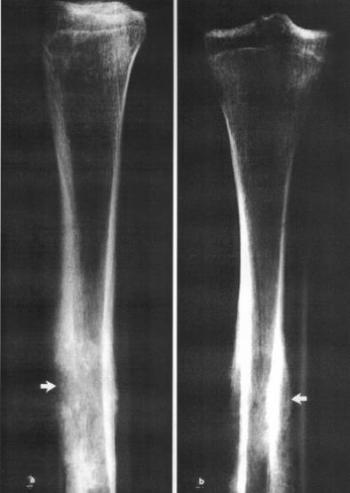

A fogeredetű tumorokat (odontoma, cementoma, ameloblastoma stb.) szintén a jóindulatú csontdaganatok közé számítják. Regöly-Mérei 1962-ben még azt írta, hogy ilyen tumort nem találtak ásatag anyagban. Azóta néhány esetet közöltek, de az ismert odontogén tumorok száma ma is 10 alatt van. A 10–12. századból való (Mongóliában előkerült) női koponyán 6x4 cm. nagyságú, a bal arcfelet deformáló tumort észleltünk. A rtg- és CT-vizsgálat a maxillát és a szájpadcsontot érintő, belsejében foltos felritkulást mutató elváltozást igazolt, amelyben fogmaradványok nem voltak (61. ábra, 62. ábra). A szövettani és elektronmikroszkópos vizsgálat cementomát (annak ossificaló variánsát) igazolta (63. ábra, 64. ábra).

62. ábra. a) A számítógépes rétegvizsgálat (CT) homloksíkú szeletén jól látszik, hogy a tumor a maxillára és a bal szájpadcsontra terjed ki b) A vízszintes rétegekben a tumorban cystás területek mutatkoznak, de fogmaradvány nem volt kimutatható